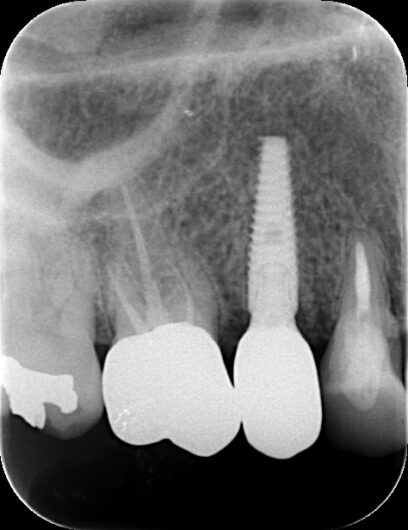

術後の検診でも順調に治癒が進み、約3ヶ月後には上部構造(人工の歯)を

装着することができました。通常の治療法であれば6〜9ヶ月かかるところを、

半分の期間で治療を完了できたのです。

4が月で治療終了